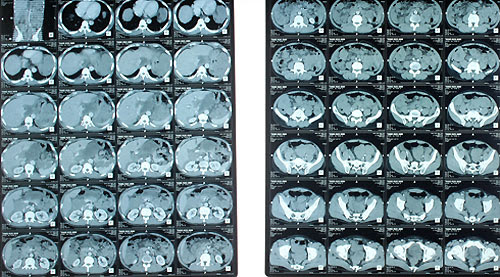

Chị gái của Joho đã kiểm tra nguy cơ mắc hội chứng Lynch giống mẹ hay không, và Joho cũng lên kế hoạch tầm soát khi cô 25 tuổi. Thế nhưng 22 tuổi, chỉ vài tháng sau khi tốt nghiệp Đại học New York, cô bắt đầu cảm thấy mệt mỏi bất thường. Bác sĩ biết về hội chứng di truyền của người mẹ nên đã yêu cầu cô nội soi đại tràng. Sau khi chụp CT, bác sĩ phát hiện một khối u rất lớn trong ruột kết của cô. Chắc chắn cô ấy đã "thừa hưởng" hội chứng Lynch từ mẹ mình.